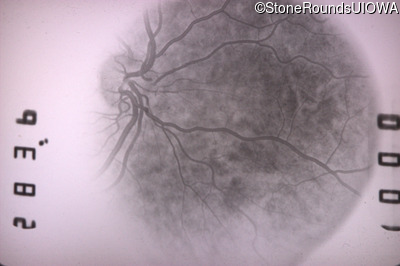

Fluorescein Angiography - Left - 20/20 -1 sc

Exemplar